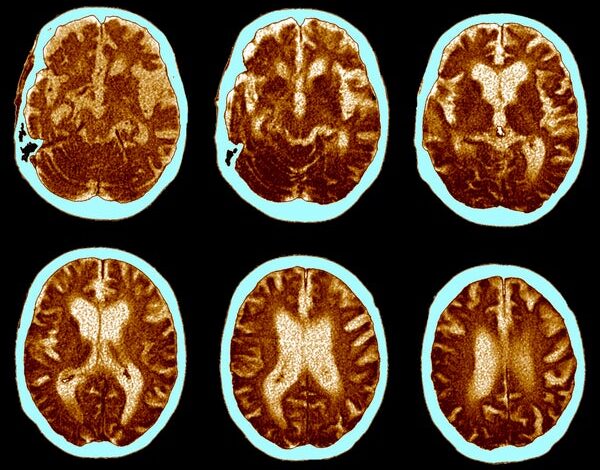

ЦТ мозга за Алцхајмерову болест.